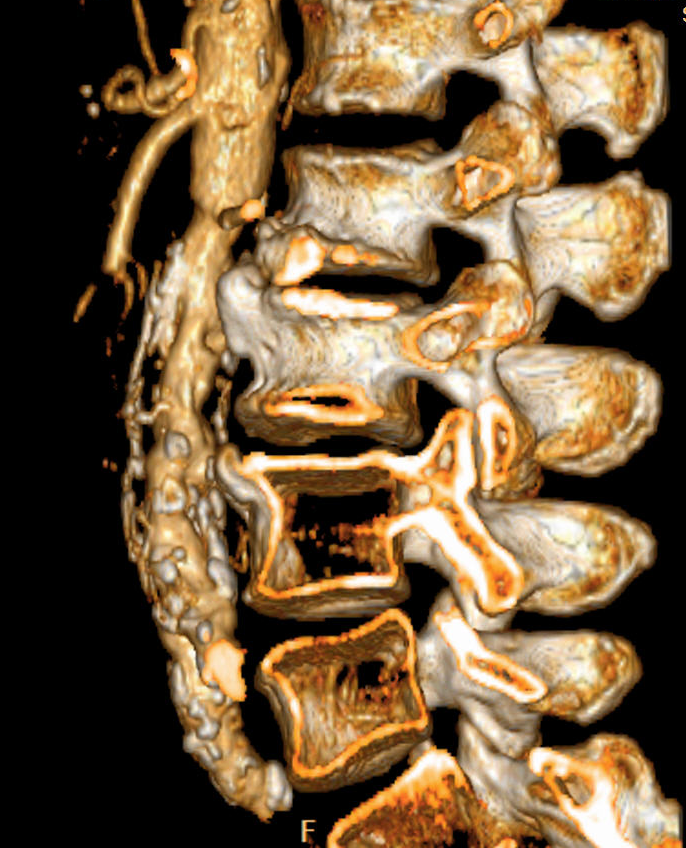

• In spinal truma CT is useful for localization of bone fragments, while MRI can visualize soft tissue structures within the spinal canal and discoligamentous injuries..

3.Back pain and decreased anal sphincter tone after motor accident. Left panel: Acute fracture of the 12th thoracic vertebra on CT. Right panel: Edema as a sign of acute fracture in the 12th thoracic vertebra on sagittal T2WI.